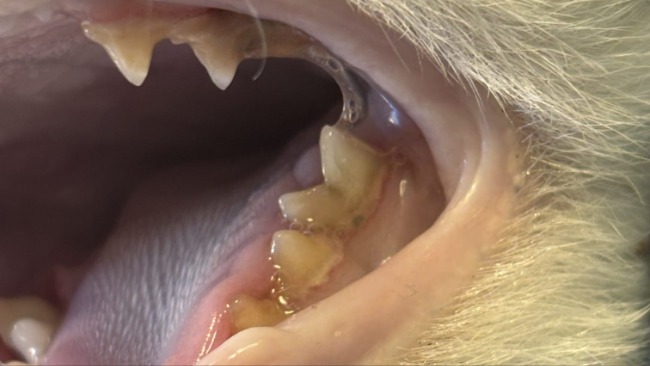

W trakcie kolejnych wizyt u weterynarza, podawanie kroplówek, leków, dalszej diagnostyki przyszedł czas na porządek w "paszczy". Trzeba usunąć kilka ząbków, zdjąć z pozostałych kamień nazębny , przepłukać dziąsła.

Powoli spływają faktury za leczenie Koleżka. Poniżej za zabieg dentystyczny .